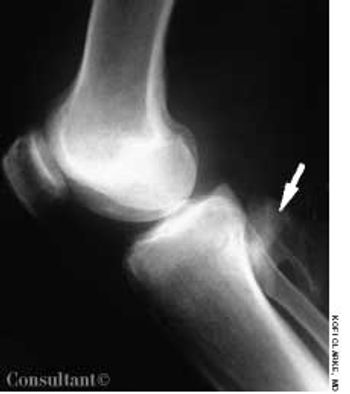

A 44-year-old man with a history of grand mal seizures experienced knee pain while walking. The pain was more severe in the left than in the right knee. The patient had a history of trauma to his left knee caused by falling during seizures.